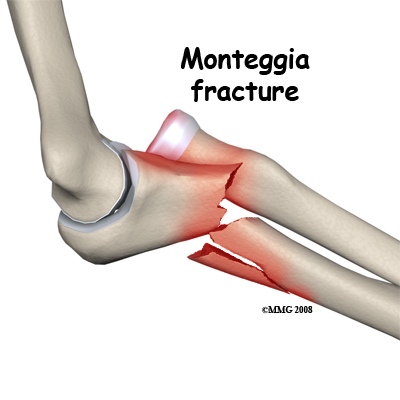

Monteggia Fracture. This fracture pattern involves dislocation of the radial head combined with a fracture of the shaft of the ulna. The mechanism of injury can be a fall with the elbow straight or a bending force on the upper part of the forearm. The shaft of the ulna breaks near the joint. There is a spectrum of damage to the radial head ranging from ligament damage only, through to joint surface damage right up to a fracture of the neck of the radius. Restoring the ulna to its correct length and orientation is the critical element in treating this injury and making the elbow stable again. For this reason an ORIF surgery on the ulna is usually undertaken in adults. The treatment of the radius depends on the extent of the injury.

Monteggia Fracture. This fracture pattern involves dislocation of the radial head combined with a fracture of the shaft of the ulna. The mechanism of injury can be a fall with the elbow straight or a bending force on the upper part of the forearm. The shaft of the ulna breaks near the joint. There is a spectrum of damage to the radial head ranging from ligament damage only, through to joint surface damage right up to a fracture of the neck of the radius. Restoring the ulna to its correct length and orientation is the critical element in treating this injury and making the elbow stable again. For this reason an ORIF surgery on the ulna is usually undertaken in adults. The treatment of the radius depends on the extent of the injury.

Monteggia Fracture of the Ulna. With a Monteggia fracture it is important to reduce the ulna fracture anatomically otherwise the elbow is prone to dislocate again. It is therefore recommended to do an ORIF operation on the bone. The shaft of the ulna lies just under the skin on the back of the forearm and can easily be exposed. The fracture is extended out to the correct length, re-aligned and rotated as necessary and is then fixed with a plate and screws. Often this treatment is all that is needed for the dislocation but if the radial head or neck is also damaged then this may also need treatment (see next section). When resting one's forearm on anything it is on the subcutaneous border of the ulna so the plate in this position is often very annoying. For this reason it is common for the plate to be removed once the injury has recovered and the bone has healed.